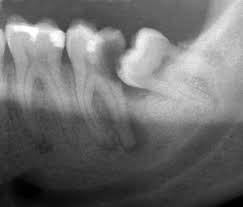

위 엑스레이 사진을 보시면 가장 오른쪽에 있는 치아가 사랑니구요, 그 앞치아가 두번째 큰어금니입니다. 두번째 큰어금니 안에 검정색으로 크게 보이는 부분이 바로 충치가 발생한 부분입니다. (출처: https://commons.wikimedia.org/)